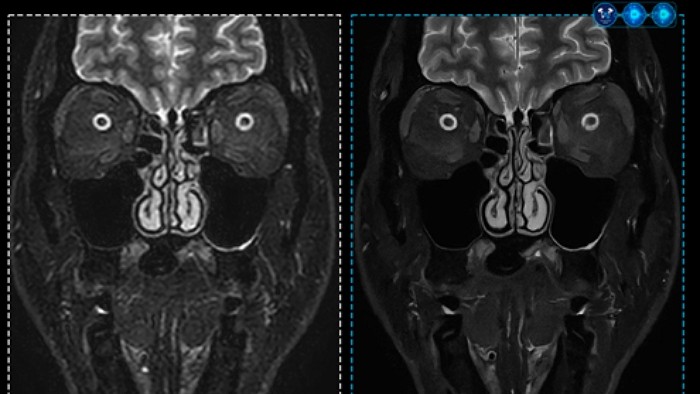

SmartSpeed Precise integrates a dual AI engine to Philips’ MR acceleration technology "Compressed SENSE," improving both scanning speed and image quality. Working from the raw data stage, a data-balancing algorithm and proprietary AI reconstruction algorithm filter essential signals while eliminating unnecessary noise during repeated reconstruction.

By combining enhanced ‘Super Resolution Algorithms’ and dual AI engines, the technology improves image resolution and signal-to-noise ratio (SNR), enhances anti-ringing features, and increases sharpness by up to 80%. This dual AI-based image reconstruction delivers scanning up to three times faster and significantly improved image quality compared to conventional methods. It supports all anatomical areas and is compatible with 97% of MR protocols, including 2D, 3D, and 4D scanning.